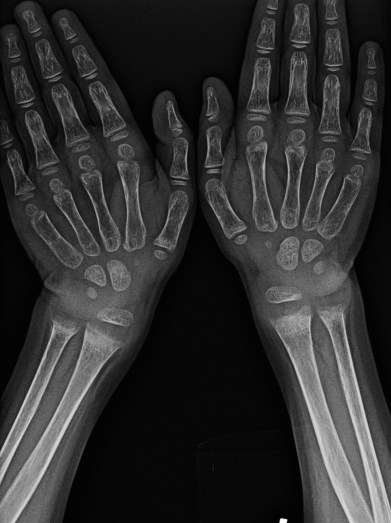

Case 3:

This is a frontal view of bilateral wrists of an immature skeleton. (Remember, bilateral views indicate a congenital or metabolic etiology; infection or neoplasm usually requires a unilateral bone x-ray).

Soft tissues and fat planes are normal. There is osteopenia with coarse trabecular pattern. The epiphyseal plate is widened (this is because the provisional zone of calcification is widened and not seen, as there is no calcium deposition happening). There is symmetric widening and fraying (brush border appearance) of the distal metaphysis of the radius and ulna. Radiological findings are consistent with rickets.

Note: You may be asked what is the bone age if the viva is going well; the distal epiphysis of the ulna is not yet present-it should appear at 5-6 years. 4 carpals are present, indicating an age of at least around 4 years. Exact bone age estimation can be done using the Greulich and Pyle atlas. Bone age may be delayed in rickets.